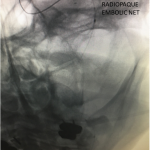

This 77-year-old man with a history of stroke in 2013 presented to a small community hospital with aphasia upon awakening. Given the unclear timing of onset of his symptoms he was not deemed a candidate for intravenous thrombolytic. His NIHSS was 2 in the emergency room. He was admitted to the hospital where a CT (Figure 1) and CTA were performed showing a left frontal small infarct and severe extracranial carotid stenosis on the left. MRI could not be performed because of the patient’s pacemaker. Examination was significant for an awake gentleman with normal cranial nerve function and normal motor exam but significant expressive aphasia. Receptive aphasia was intact. He was placed on Aspirin.

Figure 4.

Catheter angiography prior to angioplasty revealed critical stenosis (Figure 2). Angioplasty was therefore performed under local anesthesia with an embolic protection device deployed to catch any dislodged debris (Figure 3). After angioplasty, a stent was opened across the lesion to maintain long-term patency (Figure 4). Post-stent angiography showed smooth dilatation of the lesion. The patient’s aphasia continued to improve at his 6-week follow-up visit and duplex revealed no significant stenosis through the stent.